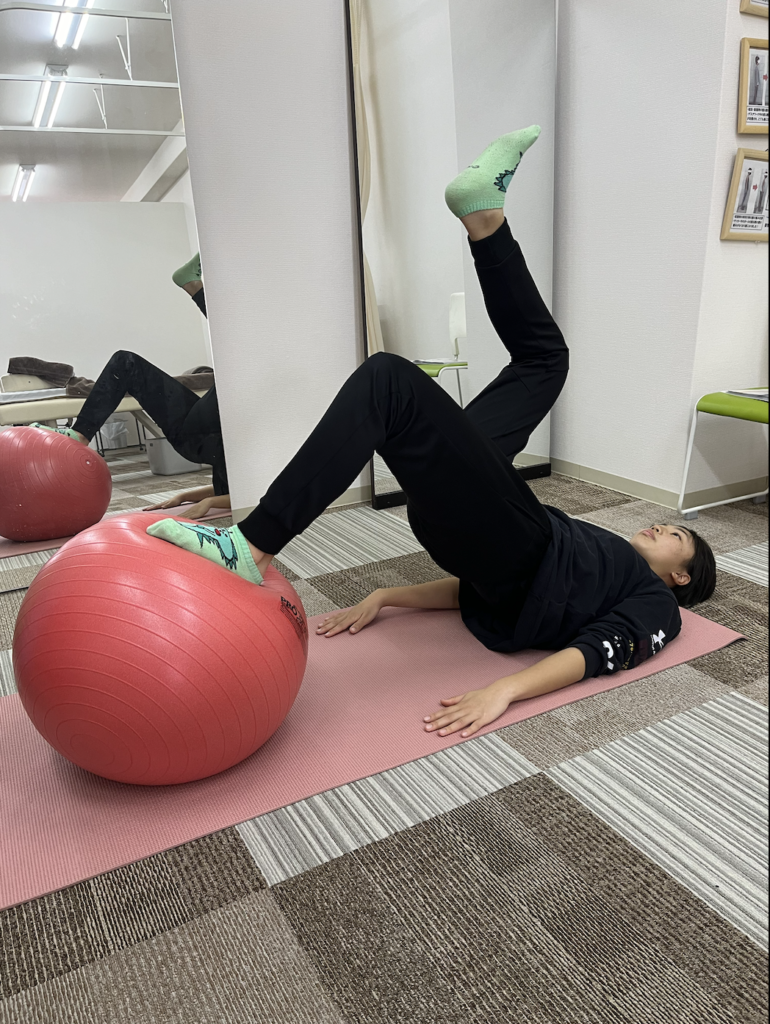

アスレチックリハビリテーションで競技復帰をサポート

アスリハとは何か

アスレチックリハビリテーション(アスリハ)とは、ケガをしたアスリートが、安全かつ効果的に競技に復帰するためのリハビリテーションプログラムです。単に痛みを取るだけでなく、ケガをする前よりも高いパフォーマンスを発揮できる体づくりを目指します。

一般的なリハビリでは、痛みが取れたら終了となることが多いですが、アスリハでは、競技に必要な動作を段階的に練習し、実際の競技場面で問題なく動けるレベルまで回復させることを目標とします。

北九州市の整骨院や接骨院でアスリハを導入しているのは、おりおスポーツ接骨院だけです。スポーツをしているお子さんにとって、競技復帰までのサポートは非常に重要です。

段階的な競技復帰プログラム

アスリハでは、以下のような段階を踏んで、少しずつ運動強度を上げていきます。

ステップ1:基本動作の確認

歩く、軽く走る、方向転換など、基本的な動作を痛みなく行えるか確認します。

ステップ2:競技特有の動作練習

バスケットボールであれば、ドリブル、パス、シュートなど、競技に必要な動作を練習します。

ステップ3:強度を上げた練習

ジャンプ、ダッシュ、ストップ動作など、より負荷の高い動作を行います。

ステップ4:実戦形式の練習

チーム練習に部分的に参加し、試合形式の動きを行います。

ステップ5:完全復帰

フルで練習や試合に参加できるようになります。

各ステップで痛みや違和感がないか確認しながら進めるため、再発のリスクを最小限に抑えることができます。

ケガをしない体づくりのためのトレーニング

アスリハでは、ケガの再発を防ぐだけでなく、今後新たなケガをしないための体づくりも行います。具体的には、以下のようなトレーニングを取り入れます。

筋力トレーニング

膝や足首を支える筋肉を強化します。特に、太ももの前側(大腿四頭筋)と後ろ側(ハムストリングス)、ふくらはぎの筋肉を鍛えることが重要です。

柔軟性トレーニング

ストレッチやヨガなどで、全身の柔軟性を高めます。柔軟性が高いと、関節の可動域が広がり、ケガをしにくくなります。

バランス・協調性トレーニング

バランスボードや不安定な地面での練習を通じて、バランス感覚と体の協調性を高めます。

プライオメトリクストレーニング

ジャンプ系のトレーニングで、瞬発力と着地時の衝撃吸収能力を高めます。

これらのトレーニングを継続することで、ケガをしにくい強い体を作ることができます。